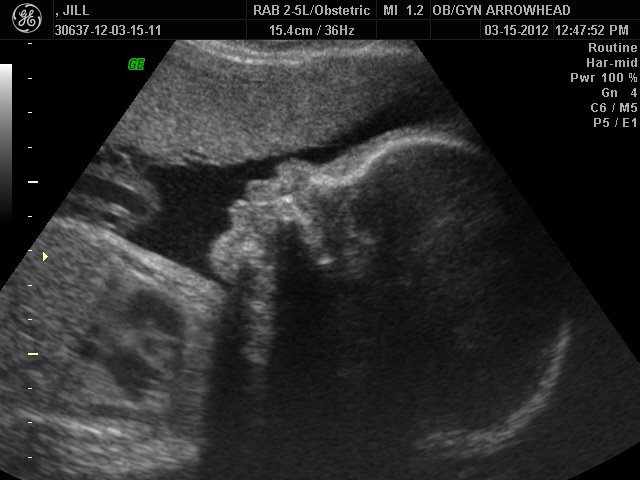

We offer complimentary 3D/4D Ultrasounds to all our OB patients around 30 weeks! The following photos are some examples of our work, shown with permission from our patients.